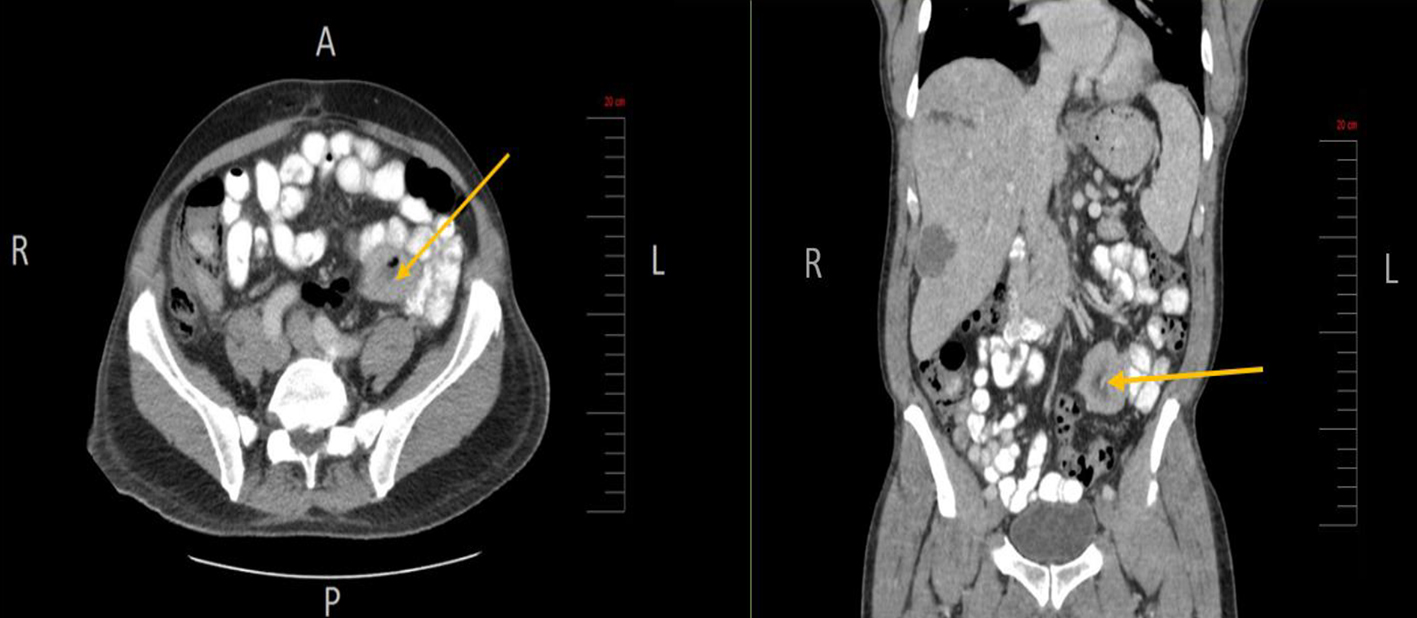

At initial presentation, his vital signs were as follows: blood pressure: 120/68 mm Hg; heart rate: 101 beats per minute; respiratory rate: 18/min; body temperature: 37.8 °C; oxygen saturation: 95% room air. Physical examination demonstrated mild tenderness in the right upper quadrant and right flank area. The patient did not have lymphadenopathy, masses or hepatosplenomegaly. On initial complete blood cell count, the white blood cell count was 13,000/µL (range: 4,500 - 11,000/µL). In addition, complete metabolic panel showed an elevated aspartate aminotransferase of 98 IU/L (range: 10 - 42 IU/L), alanine aminotransferase of 109 IU/L (range: 10 - 60 IU/L), alkaline phosphatase of 219 IU/L (range: 38 - 126 IU/L) and total bilirubin 2.6 mg/dL (range: 0.2 - 1.3 mg/dL). Hepatitis panel was negative. His erythrocyte sedimentation rate (ESR) and C-reactive protein (CRP) levels were elevated, 34 mm/h and 25.98 mg/dL, respectively. Blood and urine cultures were obtained. The patient was sent for right upper quadrant abdominal ultrasound which showed a heterogenous nodular liver with two complex masses in the right lobe, measuring 4.0 × 4.0 cm and 3.6 × 3.6 cm. The patient was started on intravenous (IV) piperacillin/tazobactam for empiric coverage. Subsequent computed tomography (CT) of the abdomen and pelvis with IV contrast revealed multiple low-attenuation lesions involving the entire right hepatic lobe, suspicious for hepatic abscesses versus cystic metastases. The largest lesion involved the inferolateral aspect of the right lobe, measuring 4.2 cm in greatest diameter (Fig. 1). A notable 4.0 × 5.7 cm small bowel mesenteric mass was also identified on imaging (Fig. 2). After discussion with the patient, surgical exploration with liver biopsy was planned.

![]() Click for large image | Figure 2. Small bowel mesenteric mass (arrow) identified on CT scan of the abdomen and pelvis (axial and coronal views, respectively). CT: computed tomography. |